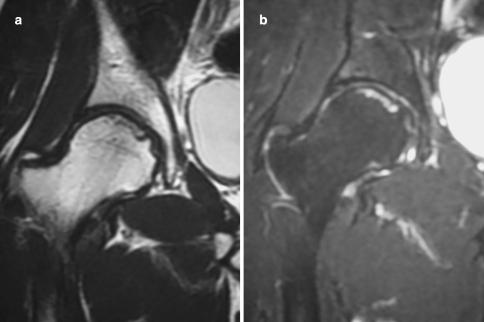

The natural history of osteonecrosis of the femoral head is generally thought to be one of progressive deterioration if no intervention is undertaken. However, it is unknown whether surgical intervention is beneficial for patients with a small region of osteonecrosis. We observed rapid improvement of MRI findings after rotational acetabular osteotomy (RAO) was performed in a young patient with osteonecrosis of the femoral head. The band-like low signal area on T2-weighted images almost resolved by six months after surgery. He returned to work as an electrician by six months after surgery. Early surgical intervention such as RAO that alters the mechanical force acting on the necrotic region of the femoral head may accelerate the recovery of osteonecrosis and the improvement of symptoms.

股骨头坏死的自然病程通常被认为是进行性恶化的,如果不进行干预的话。然而,对于股骨头坏死中存在小区域骨坏死的患者,手术干预是否有益尚不清楚。我们观察到一位年轻的股骨头坏死患者接受了旋转髋臼截骨术(RAO)后,其 MRI 发现迅速改善。手术后六个月,T2 加权图像上的带状低信号区几乎完全消失。手术后六个月,他恢复了电工的工作。像 RAO 这样的早期手术干预可以改变作用于股骨头坏死区域的机械力,从而可能加速骨坏死的恢复和症状的改善。